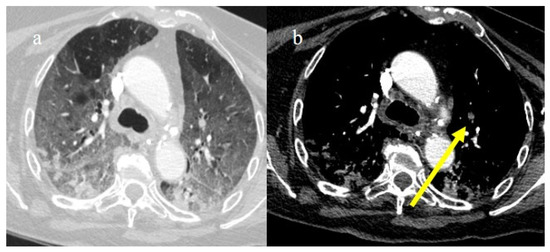

3.3.4. Pulmonary Thromboembolism

4. Vascular Abdominal Extrapulmonary Complications

4.3. Hemorrhagic Abdominal Complications